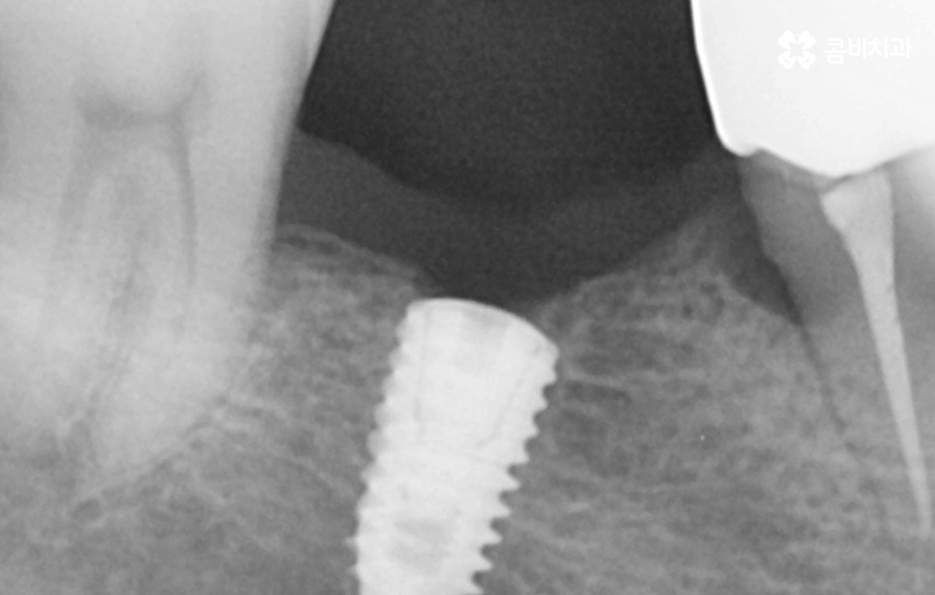

위 케이스의 노인임플란트 치료의 경우 치아의 균열부터 뿌리까지 깊어진 충치, 치주염 까지 복합적인 이유로 치아를 상실하고 여러 개의 임플란트를 식립한 사례라고 할 수 있는데요. 그래도 아직은 잔존하고 있는 치아가 많기 때문에 이미 상실한 치아에는 노인임플란트 각 위치에 맞게 적절한 치료를 받고 나머지의 자연치아에 대해서는 잘 관리하는 것이 중요한 시점이라 할 수 있어요

위 환자분의 케이스는 대부분 어금니 위주로 상실하여 노인임플란트 적절하게 식립하여 어금니의 저작기능을 수복했는데요. 노인임플란트 하면 건강보험에 대한 적용이나 저렴한 치료 비용에 대한 관심을 갖는 경우가 많긴 하지만 연령대에 따라 치아의 잔존율이 크게 급감하는 원인에 대해 잘 알아두시고 이제 치아를 하나 둘씩 잃기 시작했다면 이 시기부터 보다 적극적으로 자연치아를 보존하는 방법을 잘 숙지하시고 특히 주기적으로 치과 검진과 스케일링을 생활화 하는 것이 강조되고 있어요